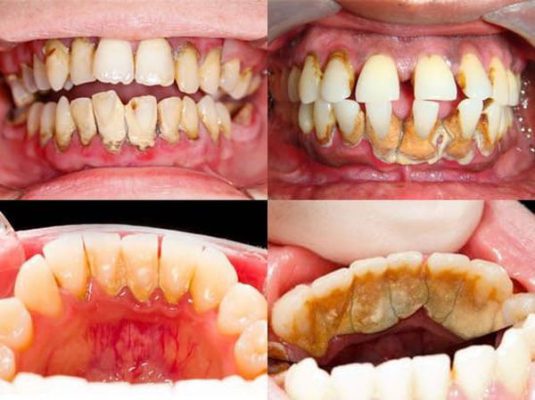

Cao răng cấp độ 1

Cao răng cấp độ 1 là giai đoạn mới hình thành. Mảng cao răng còn mỏng và có màu nhạt, thường thấy một chút ánh trắng nhẹ tại khu vực đường viền nướu. Cao răng cấp độ 1 có thể loại bỏ bằng cách chải răng đều đặn nhưng không thể làm sạch hoàn toàn.

Cao răng cấp độ 2

Cao răng cấp độ 2 cứng và dày hơn so với cấp độ 1, nhưng màu sắc vẫn còn khá nhạt. Ở giai đoạn này, cao răng đã bám chặt vào răng và cần sử dụng các dụng cụ cạo vôi răng chuyên dụng mới có thể làm sạch được.

Cao răng cấp độ 3

Cao răng cấp độ 3 dễ nhận biết hơn vì đã chuyển sang màu vàng sậm. Chúng thường xuất hiện ở mặt trong của răng, dày và cứng, rất khó loại bỏ. Trong một số trường hợp, cao răng cấp độ 3 có thể xuất hiện ở mặt ngoài răng.

Cao răng cấp độ 4

Cao răng cấp độ 4 là mức độ nặng nhất. Lúc này, cao răng đã chuyển sang màu sậm hơn, thậm chí màu đen. Chúng bắt đầu tấn công chân răng, xuống xương hàm và tiềm ẩn nhiều nguy cơ nguy hiểm cho sức khỏe răng miệng.